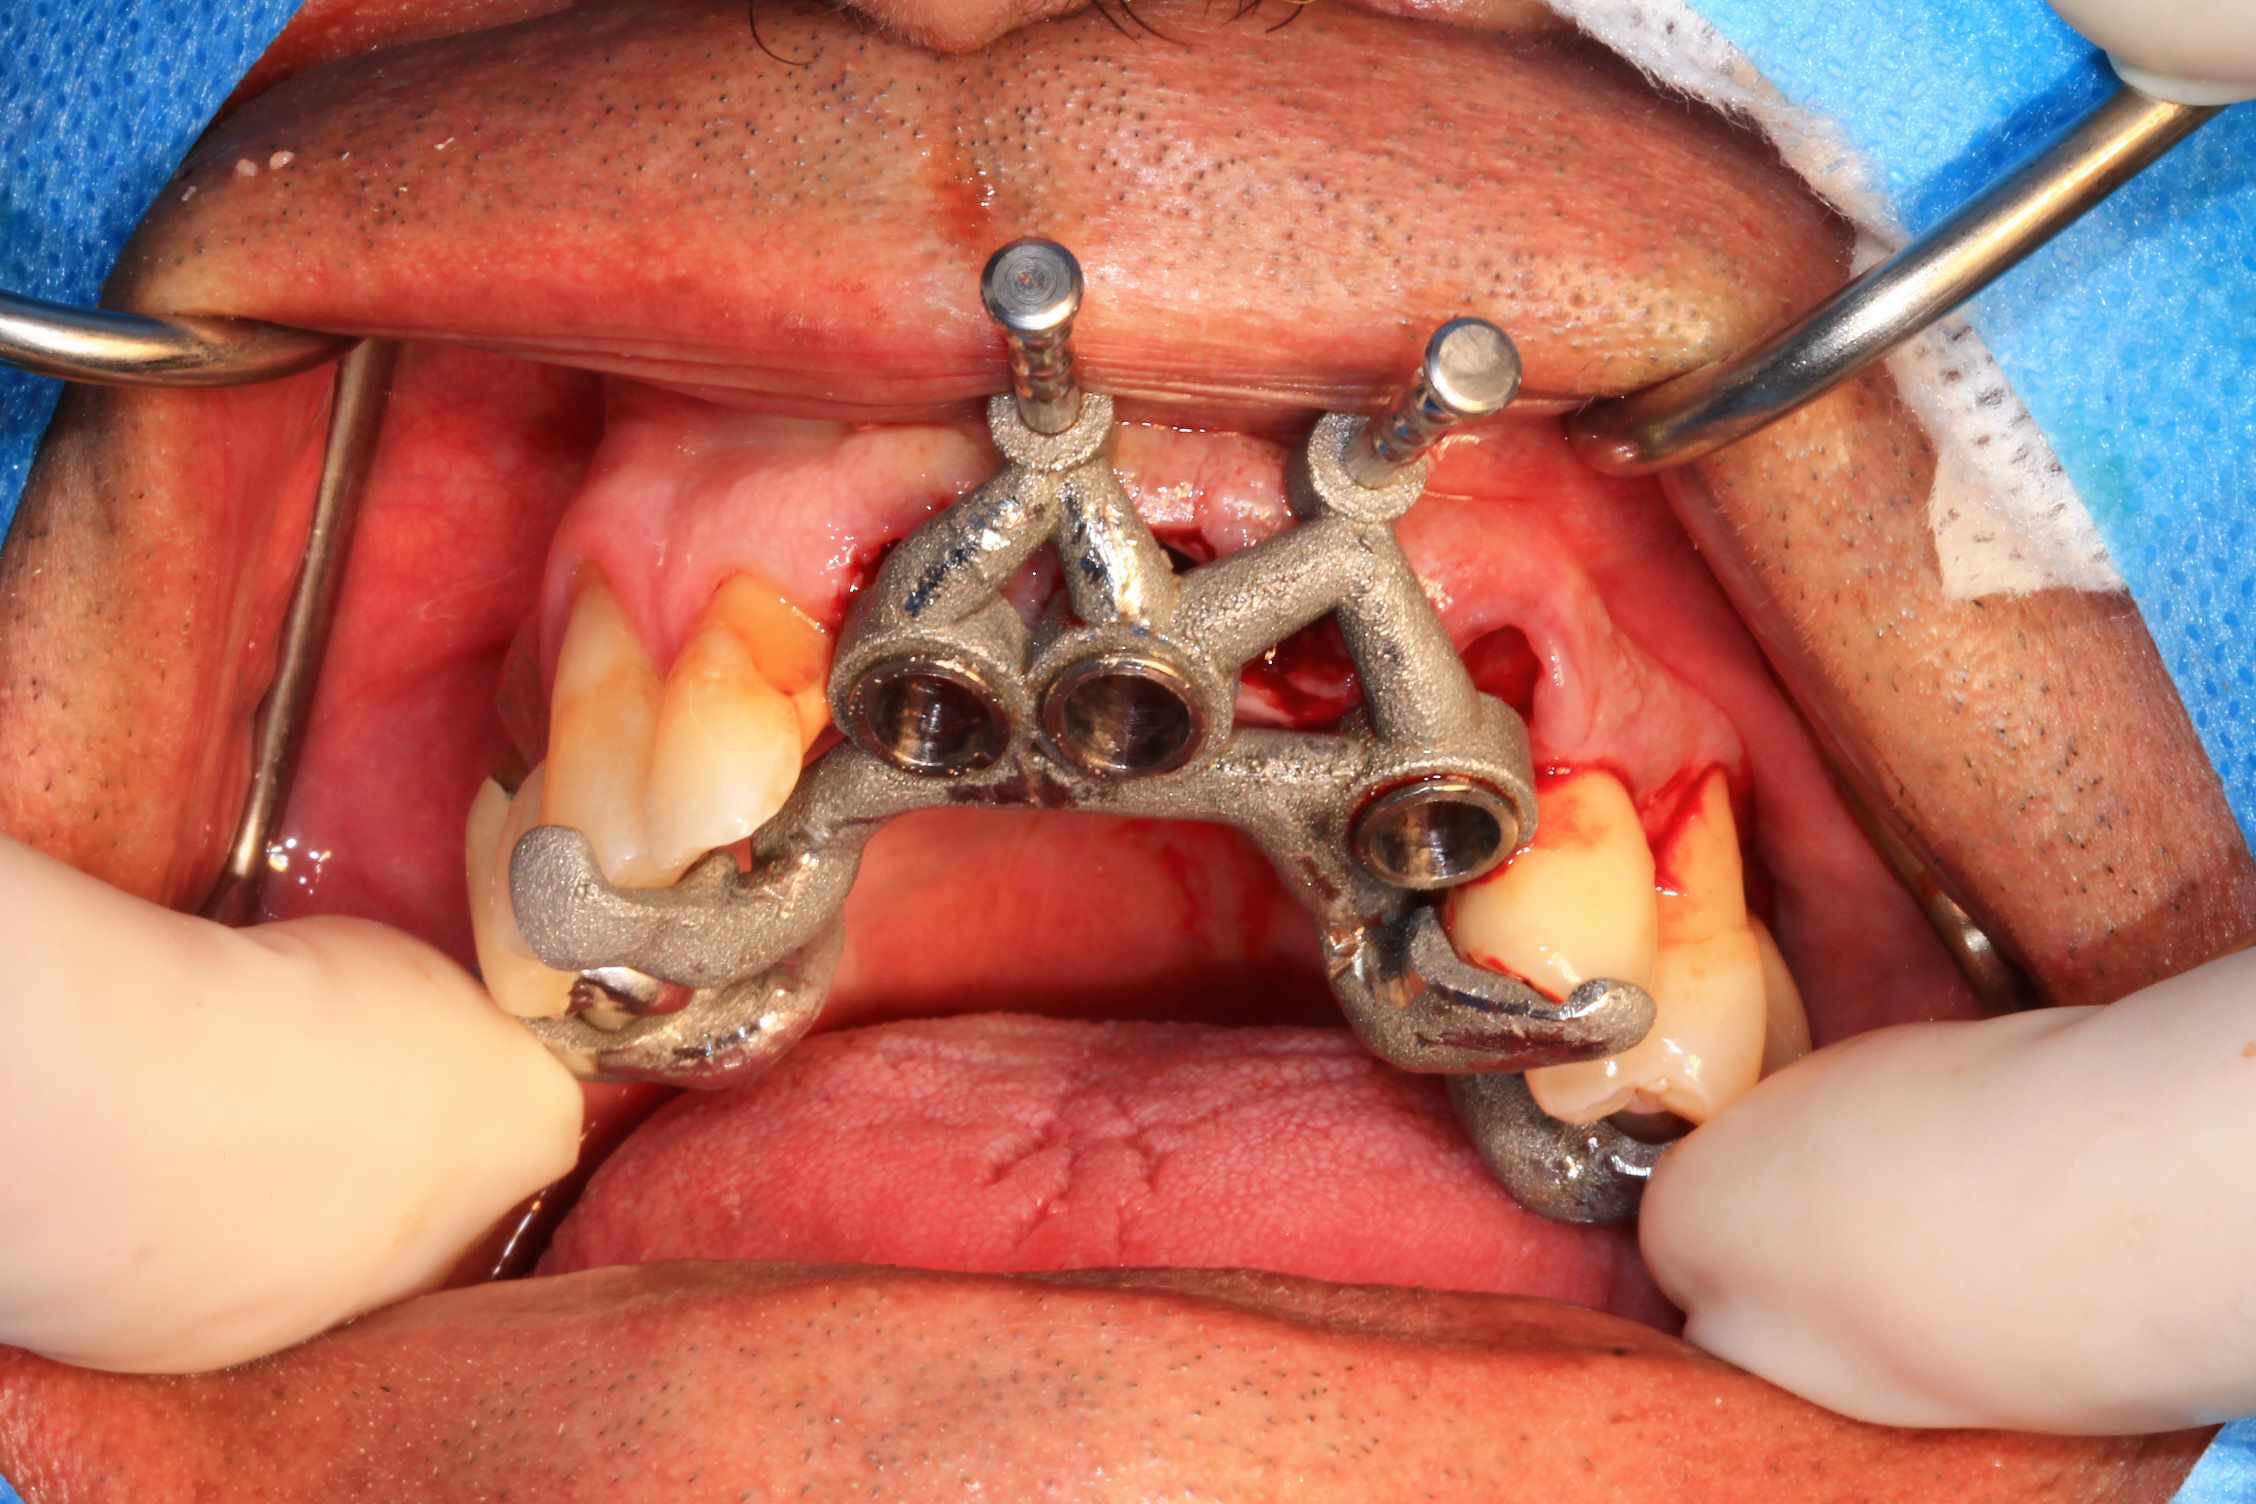

Cas 4.

Quand le mardi aprem midi, ton assistante te dit : " tout est pret pour vendredi ?" , et que tu avais simplement zappé qu'il y avait un rdv de 4 h prevu avec extraction, implantation et mise en charge immédiate, c'est la merdasse !

Donc, on rentre a la maison, on mange vite fait et on se colle au bureau. 3 heures plus tard , on va se coucher, planif, modélisation du guide et du bridge ok.

Comme pas le temps de faire un guide métal, je charge à mort les renforts pour la solidité du guide.

Le cone beam prévu : all on 4 et 4 implants en bas qui seront posé dans 3 semaines.

Le mercredi , entre mes 50 patients en ortho, j'imprime le guide et le modèle osseux. Puis le jeudi matin retour au cab ( alors que je ne travaille pas le jeudi ! ) , finition de la modélisation du bridge et impression.

Chir le vendredi matin. au vu de la possibilité de reculer pas mal les implants postérieurs, je trouvais qu'il y avait trop de porté entre les implants : je pars donc sur 6 implants.

Mais malgré les gros renforts, le guide résine n'est pas assez rigide : impossible de poser le bridge en immédiat. obligé de fraiser le bridge ( j'aurais du en prévoir un autre évidé, ce que je prévois pour lundi prochain ) et de mettre des piliers provisoires : 40 m de travail de labo en plus..